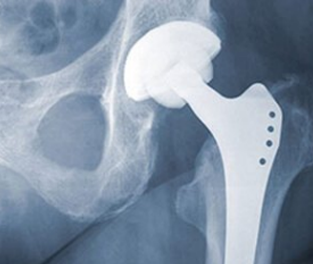

Total Hip Replacement

A total hip replacement uses an artificial joint to replace the entire hip structure. During the

procedure, surgeons insert the hip stem into the patient’s femur for stability, replace the head of the femur with a ball and replace the socket with an artificial cup. Total hip replacements are the most common type of hip replacement surgery.